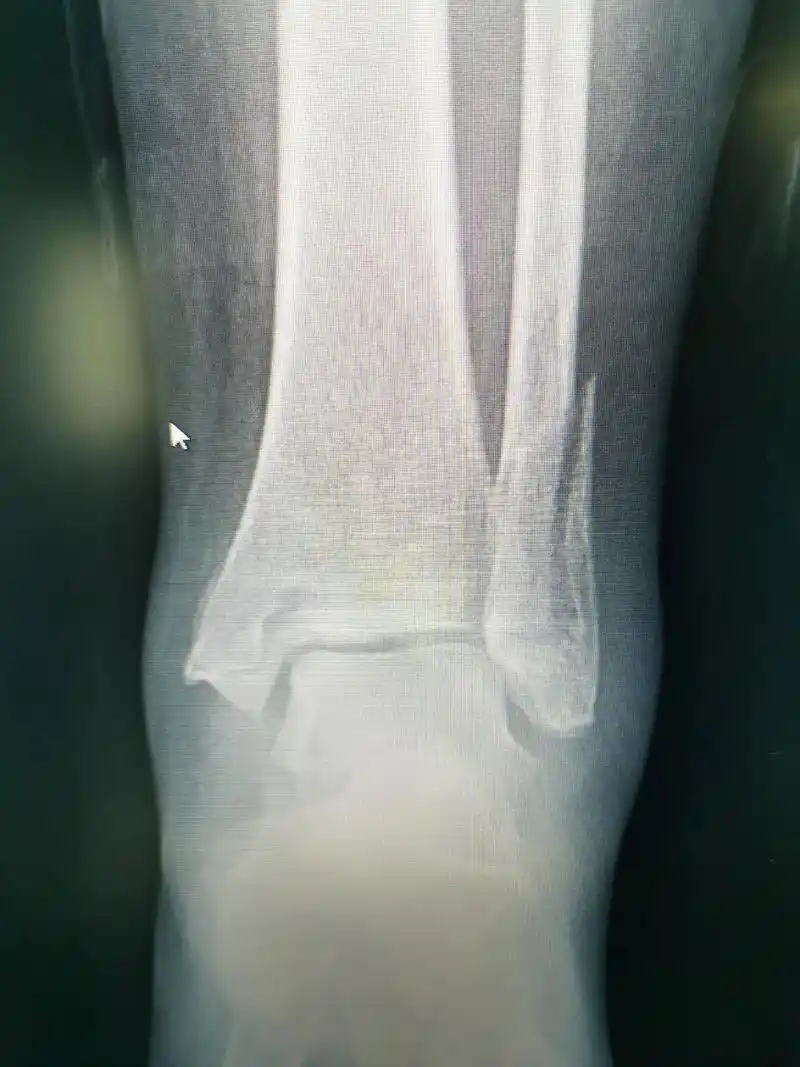

本例患者扭伤所致,踝关节 - 抖音

上午高绪仁足踝关节镜门诊经典病例踝关节扭伤骨折伴韧带损伤